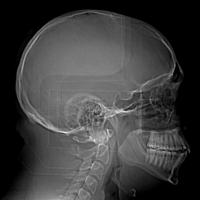

Here are a few shots illustrating how off-kilter my septum is. That line right down the middle is the septum, and it is supposed to be pretty straight. Mine, however, veers off to the left side of my body (the right in the pictures), includes a funky hook-shaped spur, and the whole nasal space is sort of off-kilter and asymmetrical. But it’s nothing that a little modern medicine can’t fix. The last picture has nothing to do with my septum, but I think it’s the coolest image on the my entire C/T scan disk.